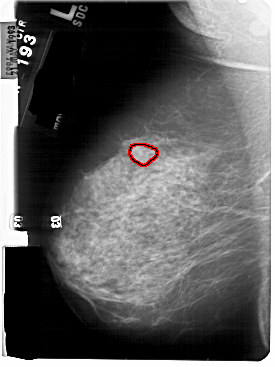

FILE: A_1834_1.LEFT_MLO.OVERLAY

TOTAL_ABNORMALITIES 1

ABNORMALITY 1

LESION_TYPE MASS SHAPE LOBULATED MARGINS OBSCURED

ASSESSMENT 4

SUBTLETY 4

PATHOLOGY BENIGN

TOTAL_OUTLINES 1

BOUNDARY

LEFT_MLO LINES 5491 PIXELS_PER_LINE 4111 BITS_PER_PIXEL 12 RESOLUTION 43.5 OVERLAY